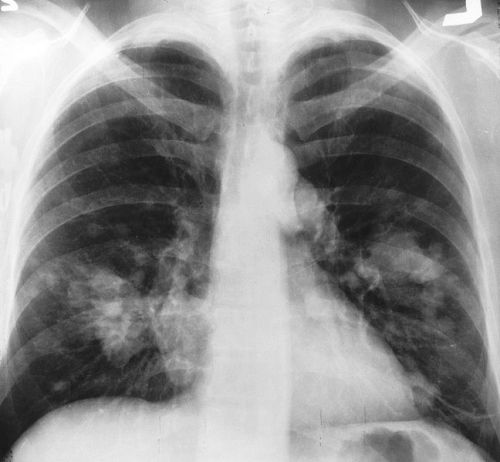

Smettete di fumare. Guarda qui cosa vi mettete nel corpo con la nicotina.